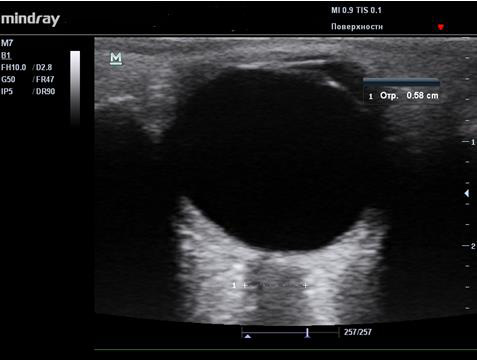

После перенесенного острого гнойного менингита в 5−10% случаев в зависимости от этиологии заболевания развивается эпилептический синдром [3, 10, 11]. В диагностическом процессе у таких детей помимо применения электроэнцефалографии показано проведение экспертной магнитно-резонансной томографии с детализированной визуализацией коры и субкортикальных отделов, а также области гиппокампов с целью исключения очагов фокальной кортикальной атрофии (рис. 4).

Рис. 4. Пациент Р., 5 лет: атрофия и фокальные корковые дисплазии на структурной магнитно-резонансной томографии. А−В ― фокальная кортикальная дисплазия в полюсном отделе правой лобной доли в виде нечеткого участка, распространяющегося от коры до переднего рога правого бокового желудочка; Г−Е ― кистозно-глиозно-атрофические изменения в правой лобной доле с викарным расширением правого бокового желудочка как исход ранее перенесенного менингоэнцефалита.